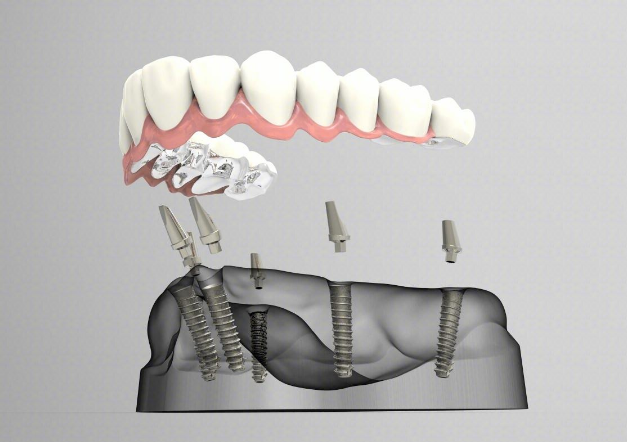

唔少長者因為年紀或者牙周病嘅情況導致半口甚至全口無牙,因香港植牙價錢好貴同埋排期好耐,所以大家有計劃到深圳半口植牙,維港口腔植牙主任為大家總結,深圳半口植牙要提前瞭解呢2個因素!

並唔系所有牙醫都具有植牙嘅專業技能,而半口植牙嘅難度更大。需要做半口植牙嘅患者牙槽骨狀況通常都唔理想,所以更加具有挑戰性,因此必須選擇技術優秀且經驗豐富嘅牙醫進行手術。另外,半口植牙難度在於需要多專業分工嘅團隊合作,並非僅僅由植牙醫生一人完成。呢需要匯聚各領域嘅專業人才,包括修復醫生負責設計理想嘅假牙和咬合方式,而經驗豐富嘅牙技師係可以用精湛嘅手藝製作出美觀且耐用嘅假牙。

種植牙嘅掂與否與植體系統嘅選擇有關,呢將直接影響植牙嘅使用壽命。優質嘅植體能夠與牙槽骨堅固結合,確保植牙長久耐用。半口植牙手術嘅效果並非一成唔變,因此需要考慮植體系否提供質保以及質保期多長,呢個系長期使用嘅一個重要考慮因素。